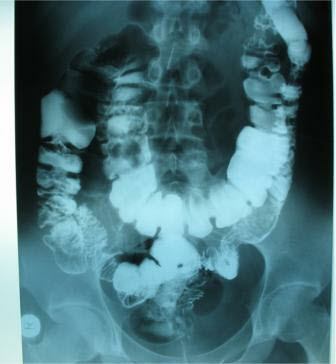

Диагностика

Для диагностики заболевания обращаются к гастроэнтерологу. Для начала пациента осматривают, пальпируют область живота и опрашивают. Затем назначается ряд процедур и обследований:

Чем обширнее поражение, тем больше исследований может понадобиться, чтобы максимально точно увидеть картину заболевания и назначить эффективную программу лечения.